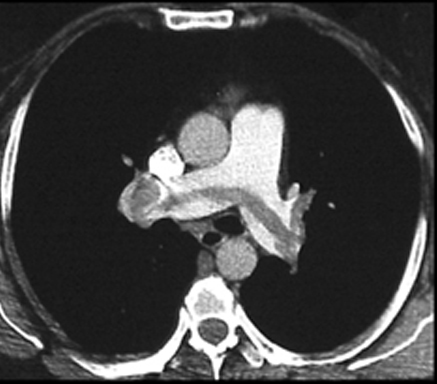

Saddle Embolus

Embolus at the level of division of left and right pulmonary arteries.